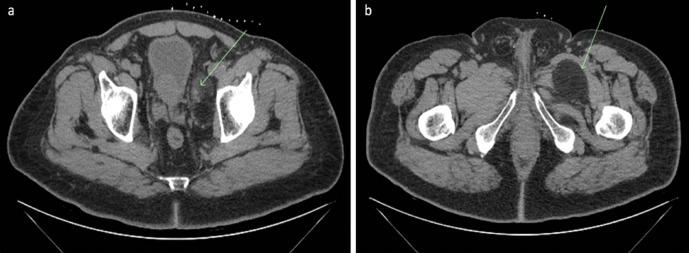

Hibernomas are a very rare and benign soft tissue tumour that originate from brown adipose tissue. While they are not histologically malignant, they may be indistinguishable from aggressive tumours such as liposarcomas on imaging. It is, therefore, important to consider it as a differential diagnosis when a suspicious fatty lesion is seen on imaging. This may prevent unnecessary invasive surgery and patient stress. This paper illustrates the clinical presentation, radiological features, and histological diagnosis of a patient with a rare dumbbell-shaped hibernoma in the pelvis.